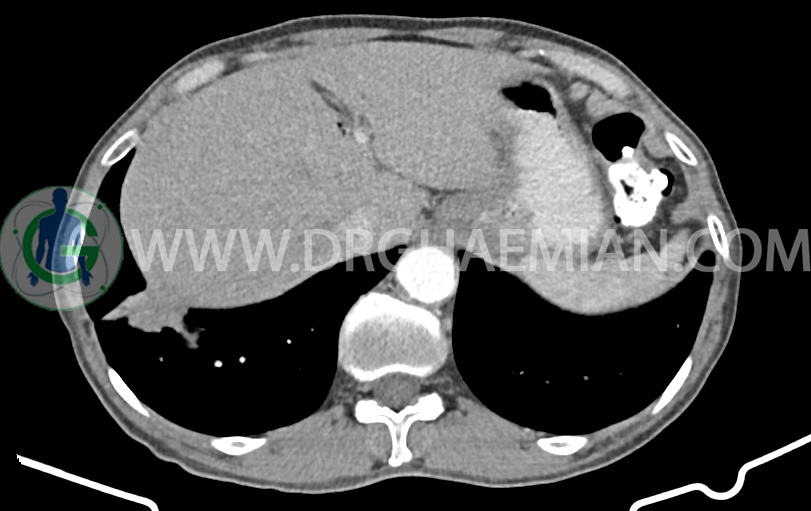

توده با حدود اسپیکوله به ابعاد mm 51x33x24 حاوی چند کانون کلسیفیه کوچک در قاعده ریه راست مجاور دیافراگم مشهود است که مطرح کننده ضایعه نئوپلازیک مثل توده اولیه و متاستاز می باشد. (نیازمند بررسی بافتی – یافته جدید نسبت به سی تی اسکن 1401/06/06 (

افزایش ضخامت ناحیه کاردیا مشاهده می شود )تطبیق با اندوسکوپی)